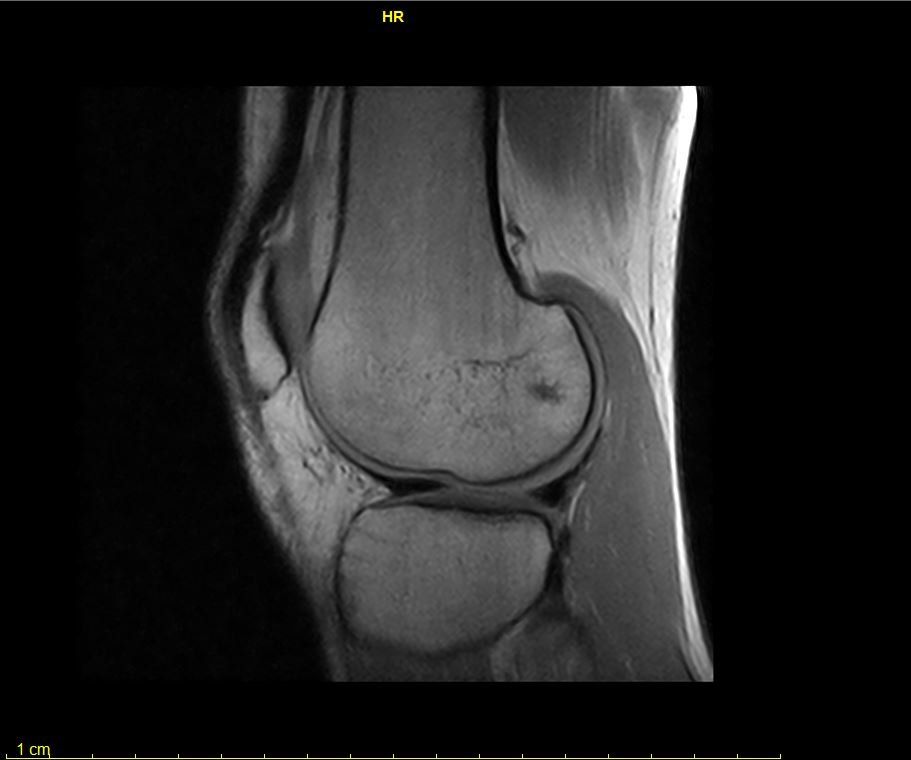

- risonanza magnetica articolare;